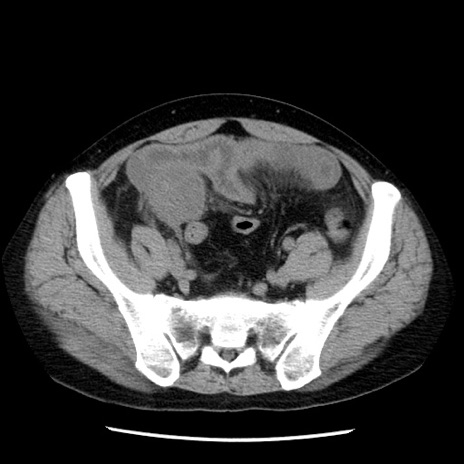

冠状断像

【症例】40歳代男性

【現病歴】2日前から胃痛あり。徐々に周期的な激痛に変化した。本日になっても激痛があるため受診。

【身体所見】意識清明、BT 38-39℃台あり、腹部:膨満、やや硬、右下腹部に圧痛あり。

【データ】WBC 8500、CRP 23.26